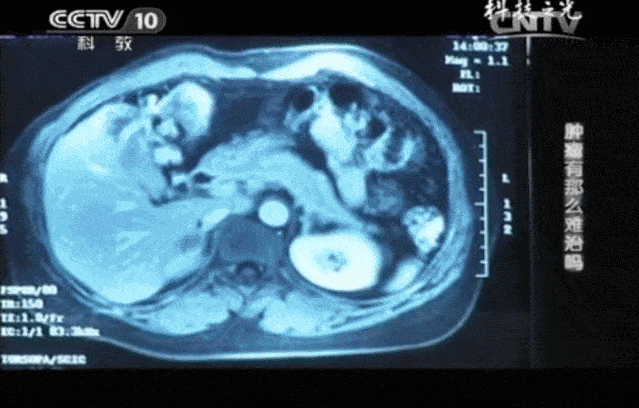

王女士的肝脏上出现了一个直径约为8cm的肝转移肿瘤。毫无征兆就出现的肝转移肿瘤让王女士彻底的绝望了。她立即决定放弃治疗,与家人一起走完人生最后的半年时间。

不仅如此,连续4个月的CT结果对比分析,肝转移瘤从8公分缩小到2.5公分,肿瘤标记物指标回归正常,这些都说明肿瘤正在被免疫细胞一点点消灭。